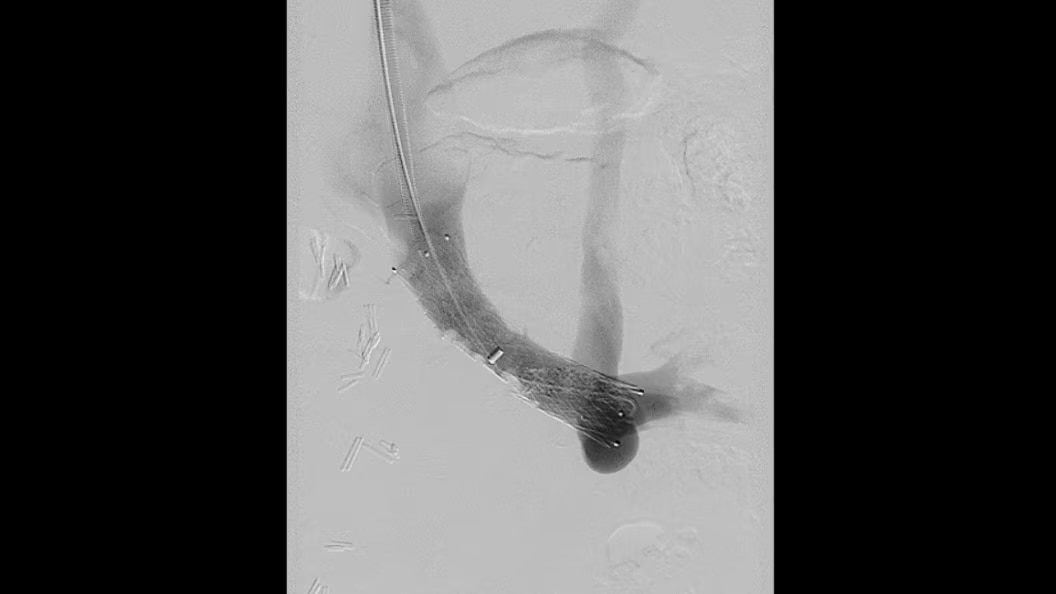

EVAR ASSIST

Perform endograft procedures in one go with intuitive tools and a simplified workflow - less radiation, more efficiency